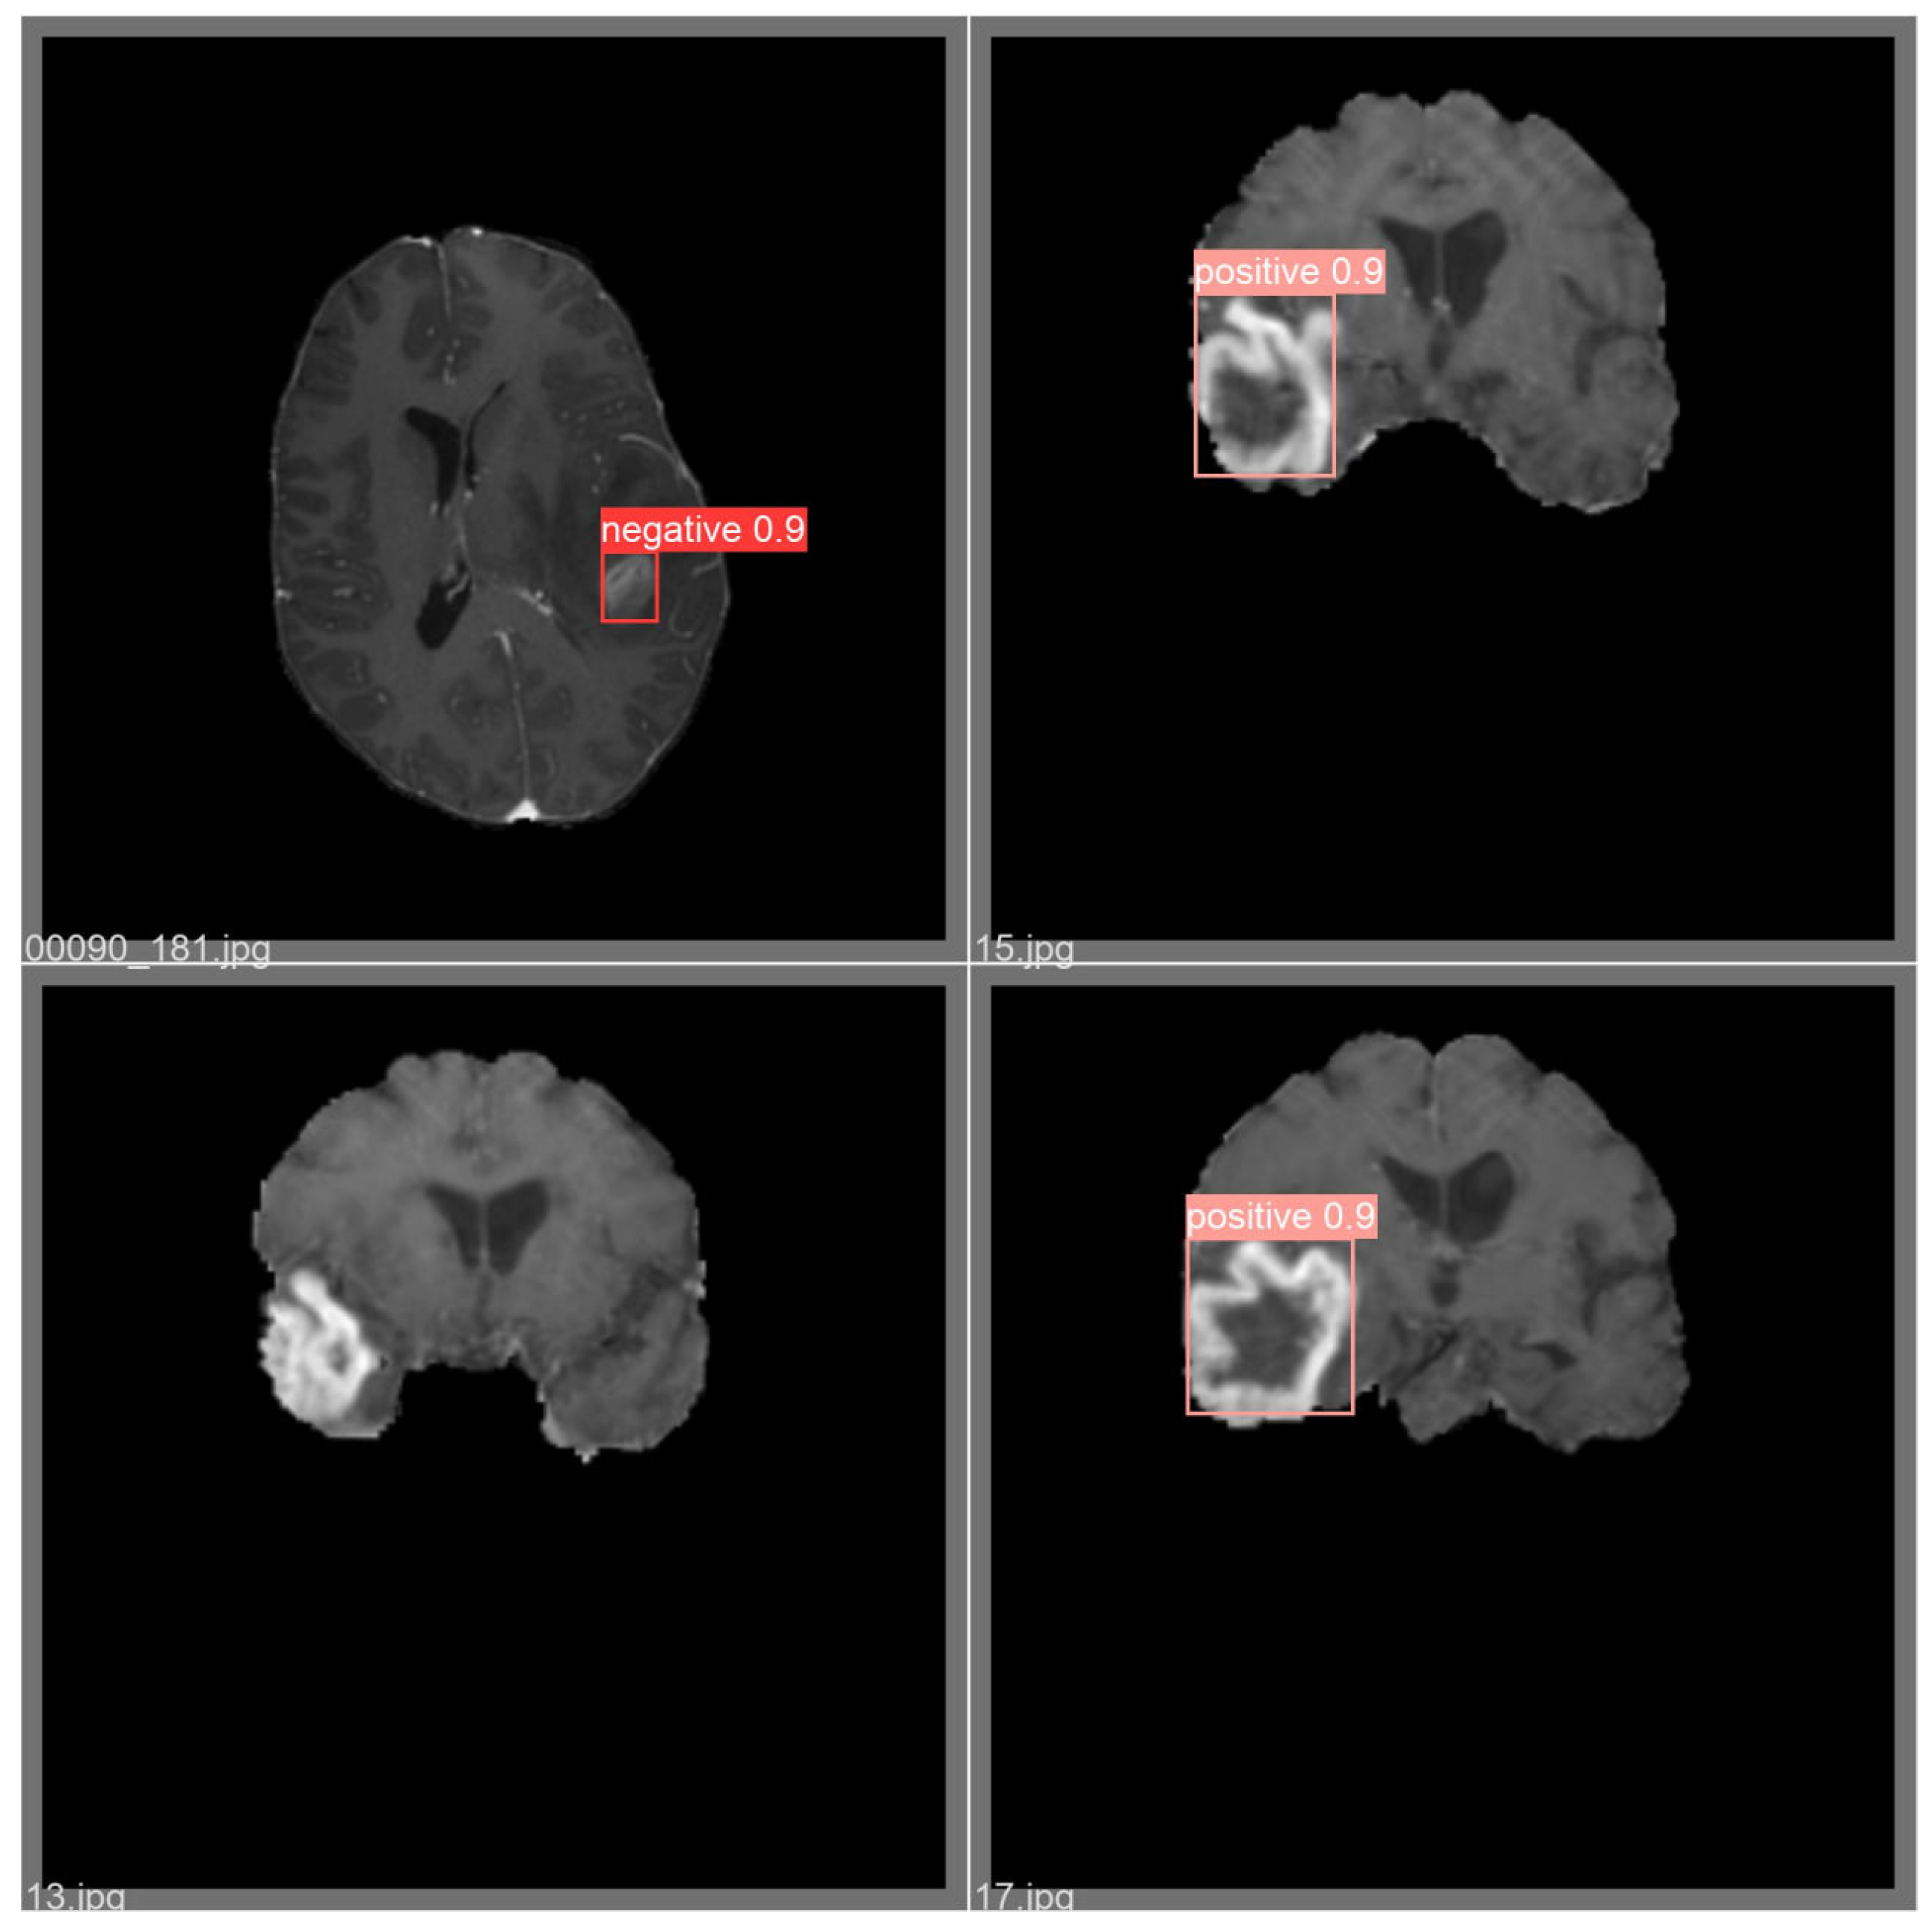

4. Experimental Results and Discussion

4.1. Overall Model Performance